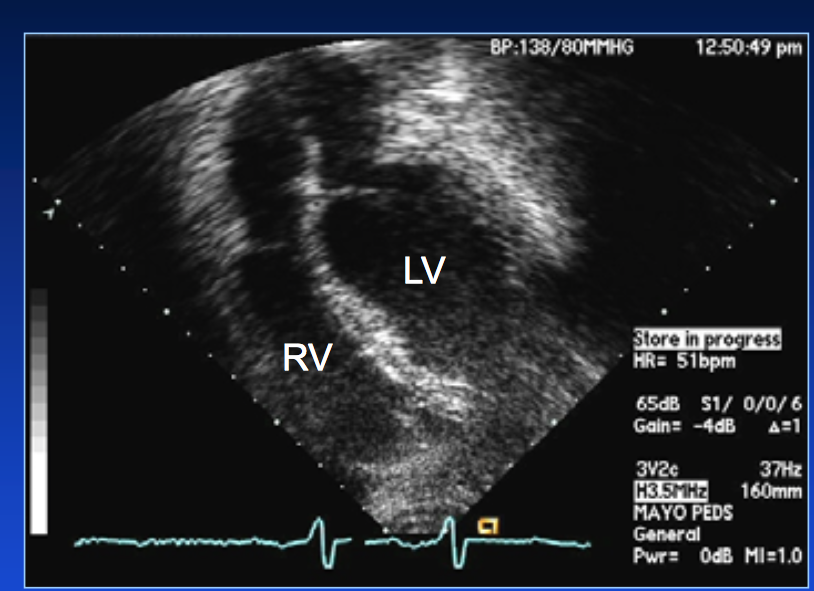

Dx?

RV dominates center of apex